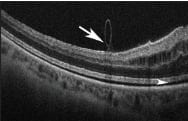

Figure 1. A partially peeled ILM using intraoperative OCT. Image obtained during surgery using a microscope mounted prototype (Bioptigen). Note the partially peeled ILM (arrow). To the left of the arrow, where the ILM is intact, the surface of the retina is smooth. To the right, where the ILM has been peeled, the surface has a feathered appearance. Note also the increased hyporeflectivity between the retina and RPE (arrowhead) following membranectomy.

Several groups are exploring the use of intraoperative OCT or iOCT for vitreoretinal surgery. Possible applications for iOCT include identification of the ILM intraoperatively without the use of dyes (Figure 1) and confirmation of complete removal of the ILM after membranectomy.23-25,44 Current prototypes of iOCT do not provide immediate surgeon feedback (ie, the surgeon cannot use iOCT to complete the membranectomy), but future models might integrate the device into the surgical microscope and allow for immediate and real-time visualization of the retinal anatomy.